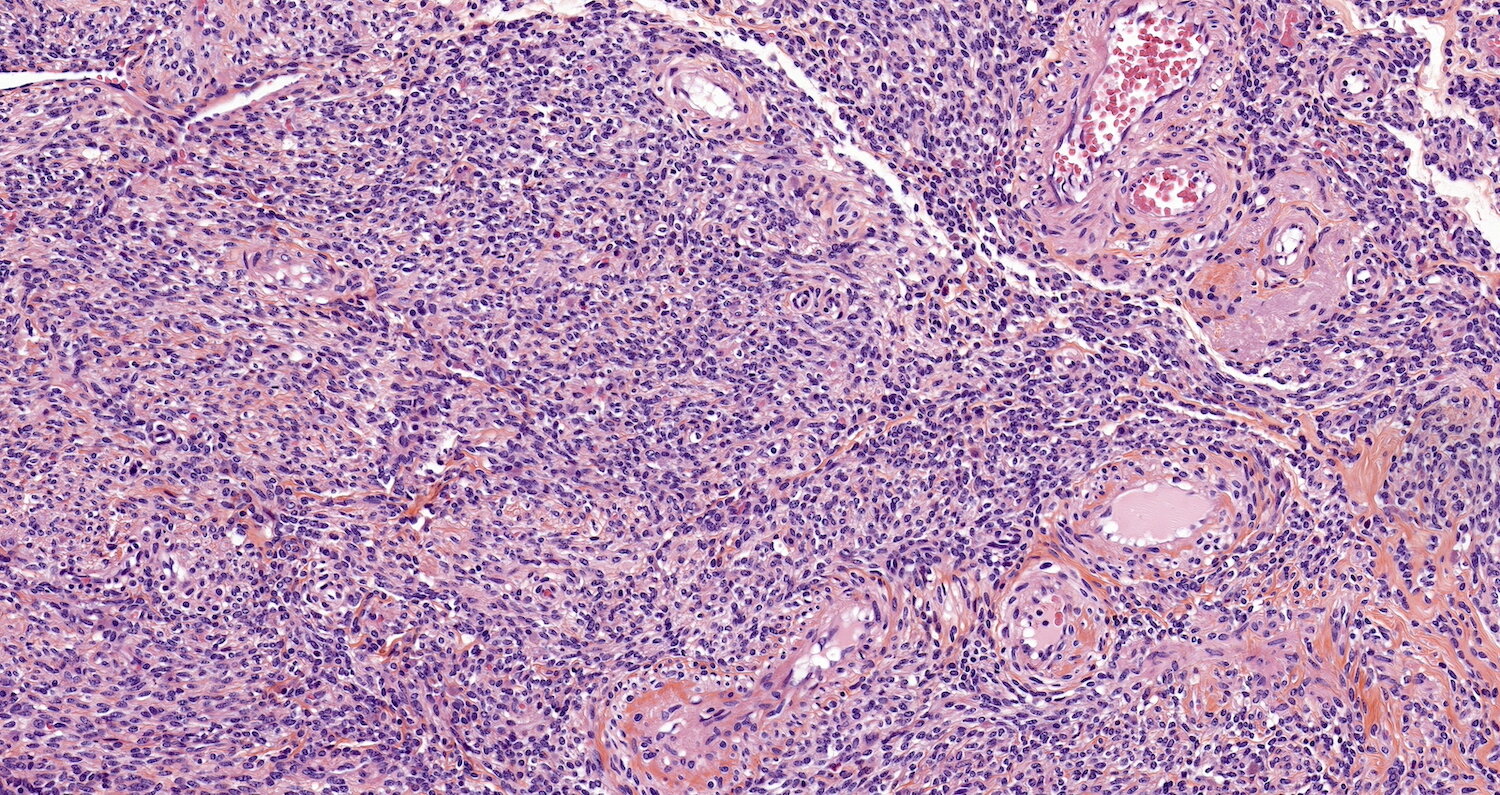

Microscopic (histologic) images

Contributed by Sabrina Croce, M.D., Ph.D., Kristina Doytcheva, M.D., Jennifer A. Bennett, M.D. (Case #508) and @Andrew_Fltv on Twitter

Microscopic (histologic) description

- Cellular

- Increased cellularity (more cellular than background myometrium)

- Scant cytoplasm without increased mitotic activity and atypia

- May have irregular borders

- Highly cellular leiomyoma is not a WHO diagnosis